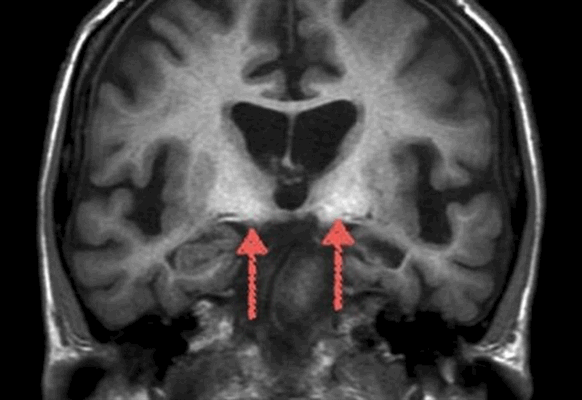

На снимках МРТ стрелками указаны участки кортикальной дисплазии - врожденного нарушения распределения клеток серого и белого веществ мозга

На МР-скане головного мозга выделен участок височного склероза, вызывающего эпилептические приступы

На магнитно-резонансном скане стрелками указаны области склероза гиппокампа